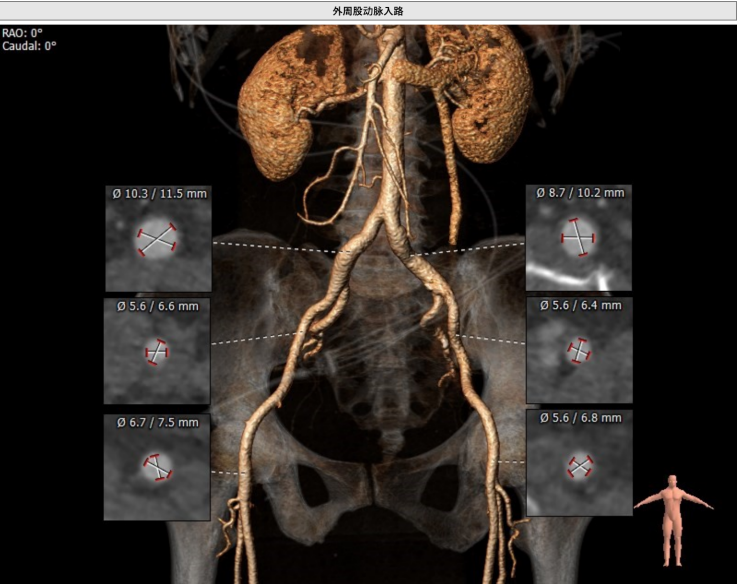

该名患者为三叶瓣,右冠窦轻度钙化。瓣环直径为23.2mm,周长为72.9mm。左冠窦中重度钙化。升主动脉稍增宽,平均直径34.0mm。左冠开口高度13.3mm,右冠开口高度15.1mm,冠脉风险低。外周血管钙化轻,入路情况较佳。

外周血管入路轻微扭曲,直径合适